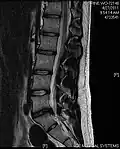

Cervical disc herniation

Herniated disc at C6–C7 level

Cervical disc herniations occur in the neck, most often between the fifth and sixth (C5–6) and the sixth and seventh (C6–7) cervical vertebral bodies. There is an increased susceptibility amongst older (60+) patients to herniations higher in the neck, especially at C3–4.[23] Symptoms of cervical herniations may be felt in the back of the skull, the neck, shoulder girdle, scapula, arm, and hand.[24] The nerves of the cervical plexus and brachial plexus can be affected.[25]